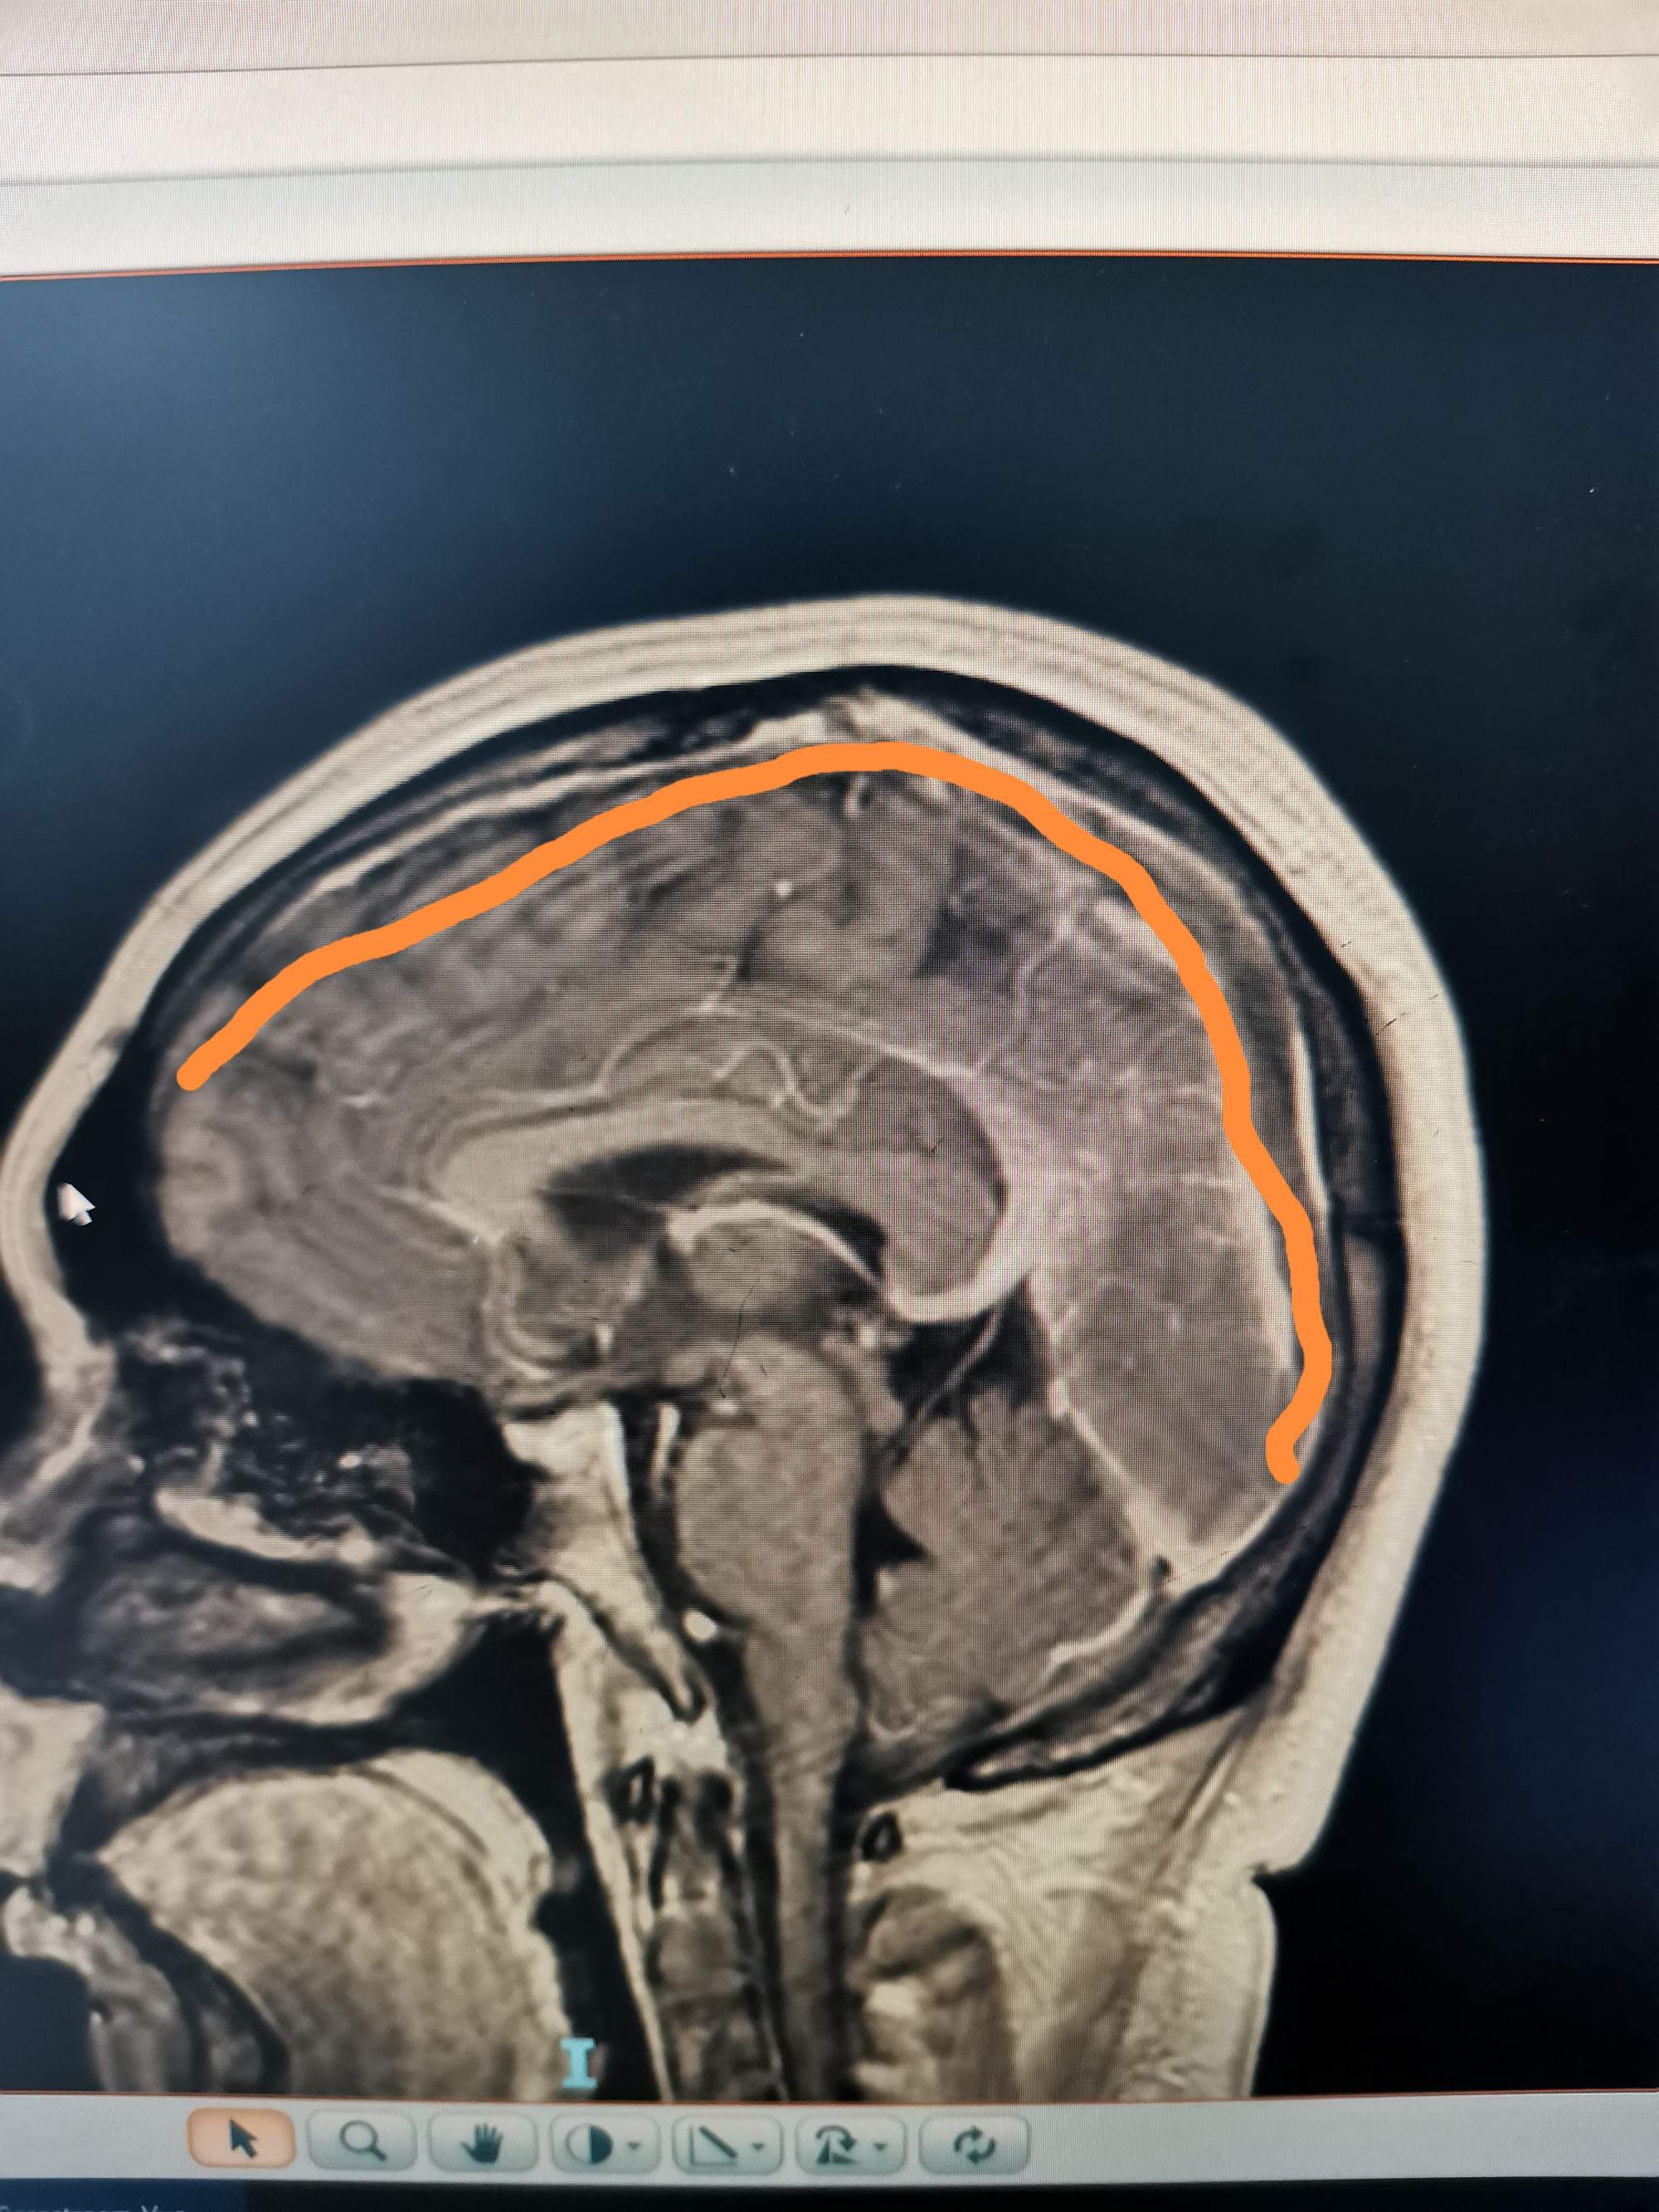

外院磁共振增强见,矢状窦局部充盈缺损。

增强显示矢状窦长节段充盈缺损,D-2聚体大于正常上限5倍以上。我科诊断考虑上矢状窦血栓形成伴多发多次脑梗死伴出血。

矢状窦全程血栓,与外院相比血栓明显扩大。立即急诊行脑血管造影+介入取栓术。

矢状窦是大脑最大的回流静脉,相当于颅内的长江,长江主干闭塞,各支流必将洪水泛滥。患者随时可能再发脑梗和脑出血可能。立即急诊行脑血管造影+介入取栓术。

患者左侧横窦优势,左侧颈内动脉造影侧位见矢状窦起始部至横窦水平未显影。